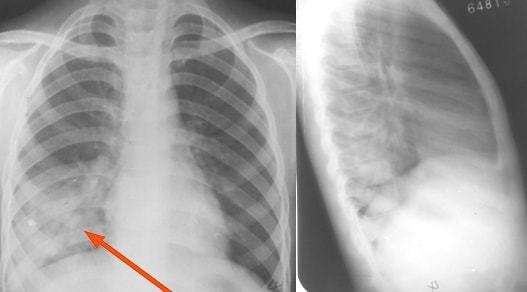

右肺下叶背段大叶性肺炎正侧位消散期:实变区密度逐渐减低,表现为大小

图片尺寸1080x648